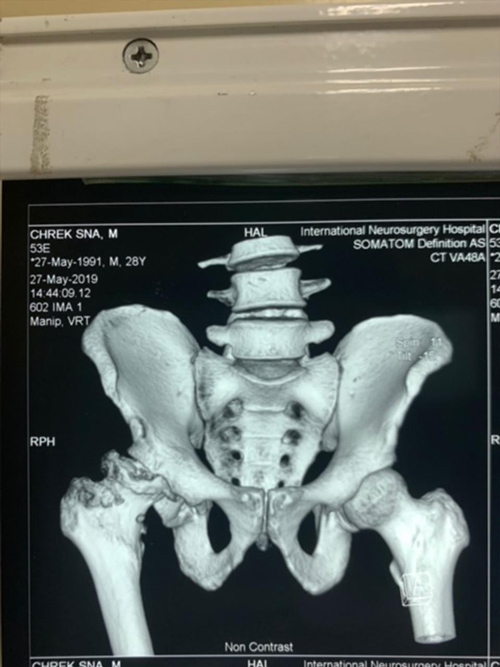

Dr. Weber and his partners participate in short term medical mission trips to Cambodia. Dr. Weber has had the pleasure of going twice now in 2018 and 2020. During these trips Dr. Weber performs total hip replacements on patients who normally would have no treatment options. To learn more and to see videos from the experience please click the links below.